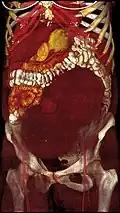

A very large (9 cm) fibroid of the uterus which is causing pelvic congestion syndrome as seen on CT -

Giant leiomyomas almost filling the abdomen -